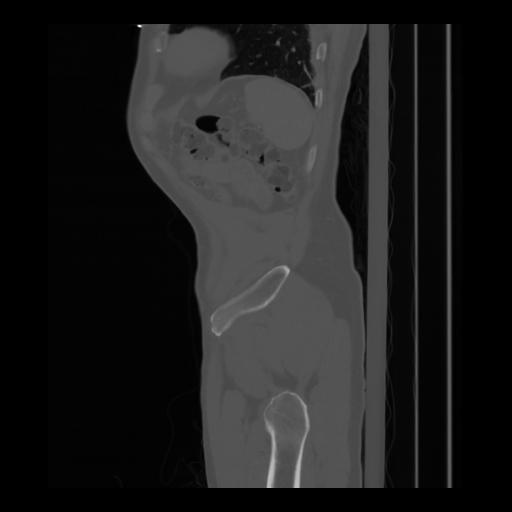

36 CUERPO,CE,Sagittal,3.000,CUERPO,Sagittal,